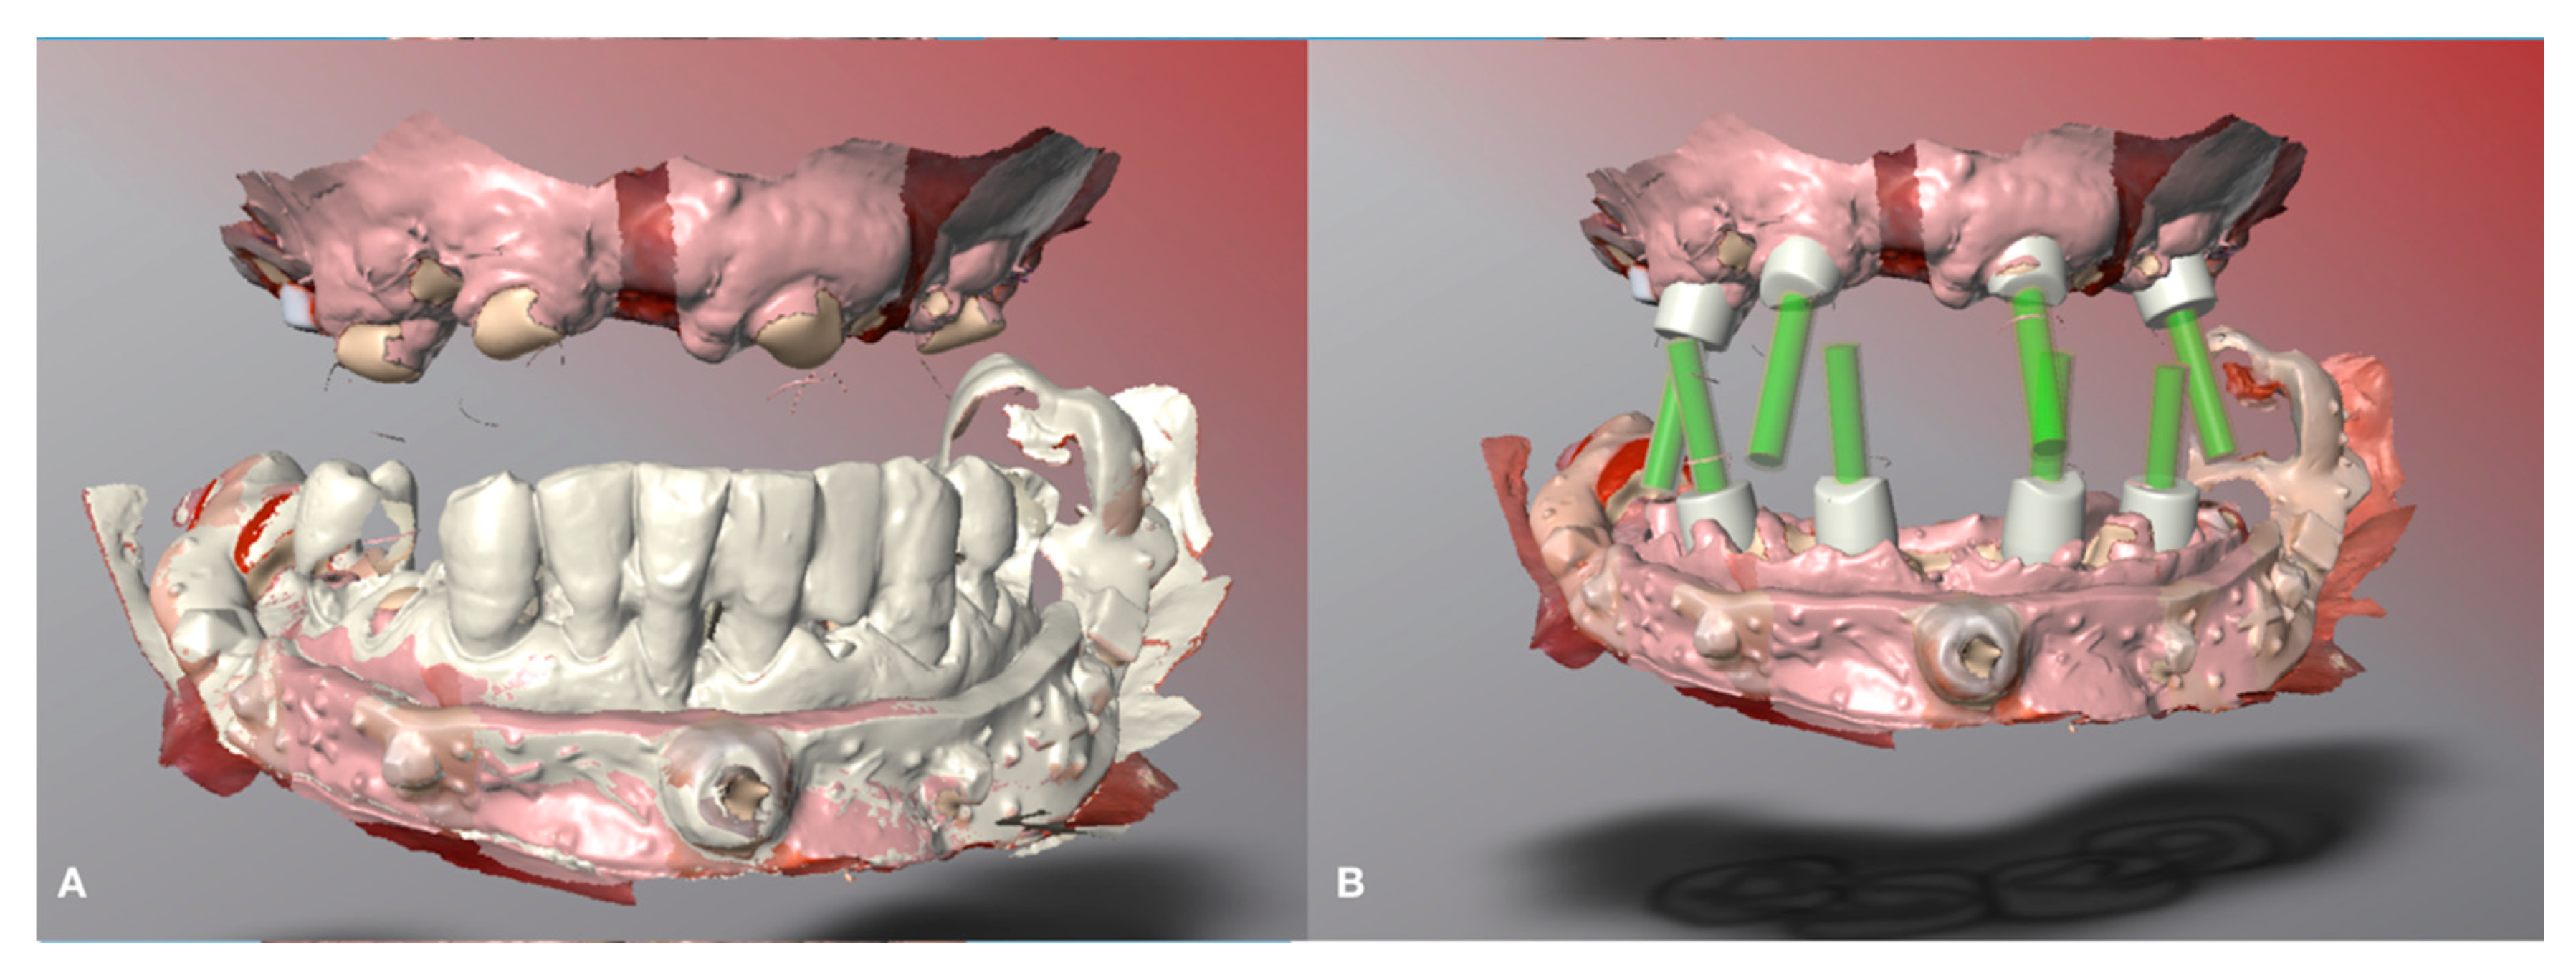

Digital lower preliminary impressions were taken (Figure 3) during the first visit using an intraoral scanner (Medit i500, Seoul, South Corea) and imported into CAD software (DWOS, Dental Wings Inc., Montreal, Canada, software version 3.7.0.26).

This technique allows one to change the vertical dimension of occlusion before the actual surgery using for example direct composite restorations on the existing dentition if present to test the desired vertical dimension changes for any clinical purpose (gnathological issues, collapsed vertical dimension and so forth). It is also possible to immediately determine an increase or any other kind of change in the maxilla–mandibular relationship using conventional techniques before digitally recording it. An example is the digital recording of the maxilla–mandibular relationship in the centric relation using an occlusal wax. In the case of a reduced number of occluding teeth proper stabilization of the maxilla–mandibular position into the centric relation is required using conventional methods before digitally recording the determined position by scanning. The described case did not require any change to the existing occlusal determinants. The next step consisted of the design of the lower acrylic resin jig, which is the digital index, on the preliminary lower impression (Figure 4) to superimpose the lower presurgical scan with the postsurgical impression.

Figure 3. Preliminary digital impression. (A) Maxillary preliminary digital impression. (B) Mandibular preliminary digital impression.